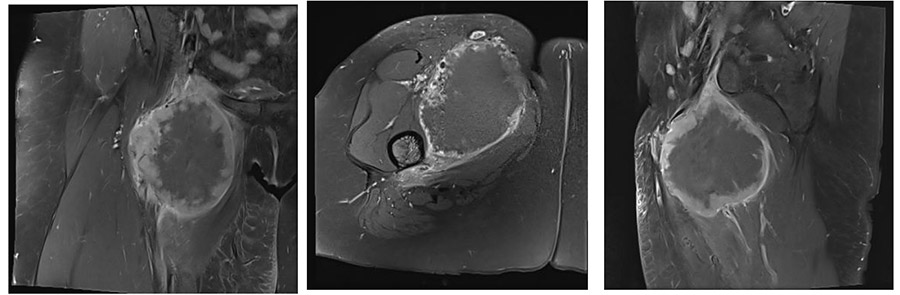

Ameliyat Öncesi: MR’da proksimal uyluk medialde femoral arter ven paketini çevreleyen düzensiz sınırlı, heterojen, mekezinde nekrozun eşlik ettiği yumuşak doku kitlesi görülmekte